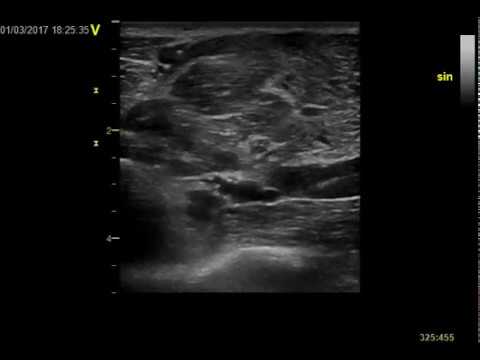

Anterior interosseous with median nerve at pronator exit. Normal nerve ultrasound.

Anterior interosseous enlargement at pronator exit. Nerve ultrasound.